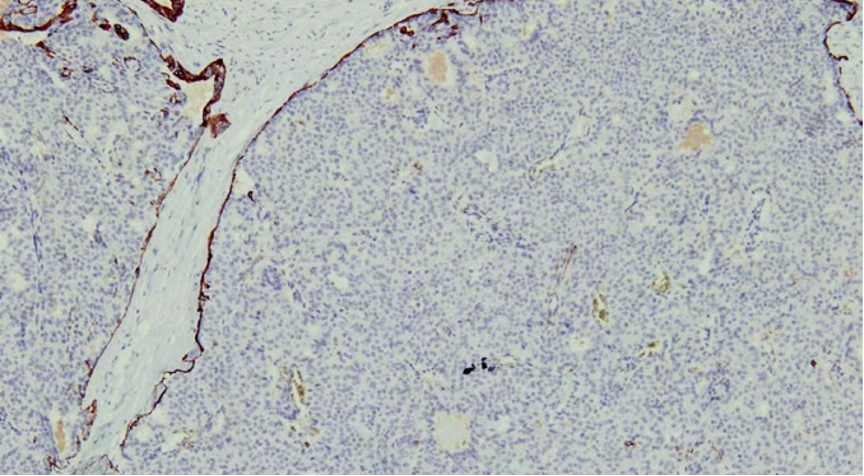

免疫组化

肌上皮内-,导管周可-可+